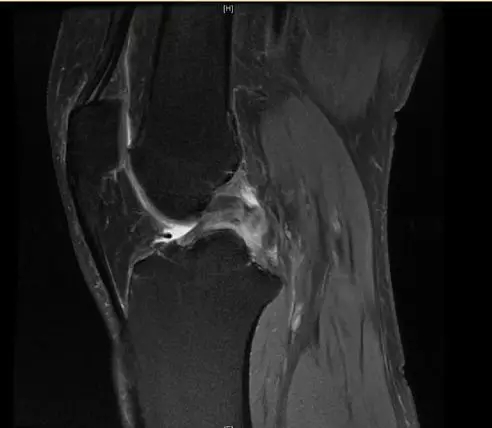

后交叉韧带断裂

从此片可以看出后交叉韧带连续性中断,松弛,增粗,下止点信号增高比较明显,从这个角度看后交叉韧带上止点信号较为正常,但下止点信号明显增高,缺乏韧带止点应有的形态,从这个层面看下止点信号增高,从这个层面看韧带是增粗的,整体信号增高,质地不均一,并且松弛,从这个层面可以看到它的下止点信号增高,缺乏正常的韧带形态特点,所以考虑后交叉韧带断裂。